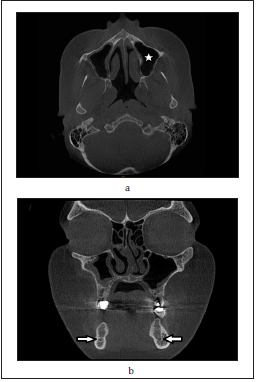

The last section of the survey included four CBCT images of partially edentulous patients that were retrieved from the records of oral and maxillofacial radiology department. Patients records were anonymous with guarantee of data confidentiality. In this section, the participants were asked to choose the type of view from four multiple choices [axial, sagittal, coronal, or panoramic], and to name the marked anatomical structure for each image (Figure 2a & 2b).

Figure 2: Examples of CBCT radiographic images showing regions of interest marked and the question was to

choose the type of view and to identify the anatomical structure marked.

a. axial view, maxillary sinus,

b. coronal view, mandibualr canal.